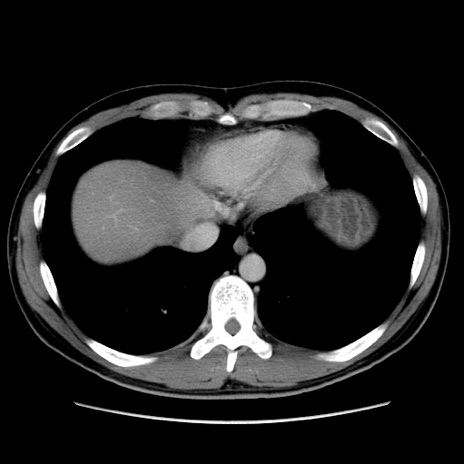

症例36(横断像)

【症例】20歳代 男性

【主訴】心窩部痛

【現病歴】今朝より上腹部痛あり。一旦軽快していたが再度出現したため救急要請。昨日夕に白身の魚を含む刺身を食べた。

【身体所見】BP 136/89mmHg、HR 74/min、BT 37.0℃、腹部:膨満、軟、心窩部に圧痛あり。反跳痛なし、筋性防御なし、腸雑音やや亢進あり。

【データ】WBC 17700、CRP 0.48